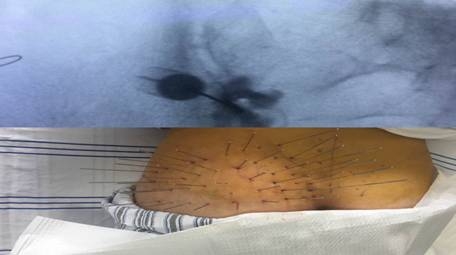

根據(jù)查體、病史收集、輔助檢查及分析討論,馮女士最終被確診為:左骶髂關(guān)節(jié)炎。醫(yī)生給予消炎止痛,緩解肌肉痙攣,中藥外敷等治療,并在局麻下施行內(nèi)熱針治療術(shù)+左骶髂關(guān)節(jié)射頻+阻滯術(shù),手術(shù)效果極其良好!

術(shù)后第二天,馮女士就自覺左腰骶部疼痛明顯減輕,心情豁然開朗!一周后,馮女士的疼痛癥狀完全消除!經(jīng)過積極的功能鍛煉,她終于可以正常走路,開開心心地回家和未滿月的小寶寶團(tuán)聚啦!

馮女士治療過程中